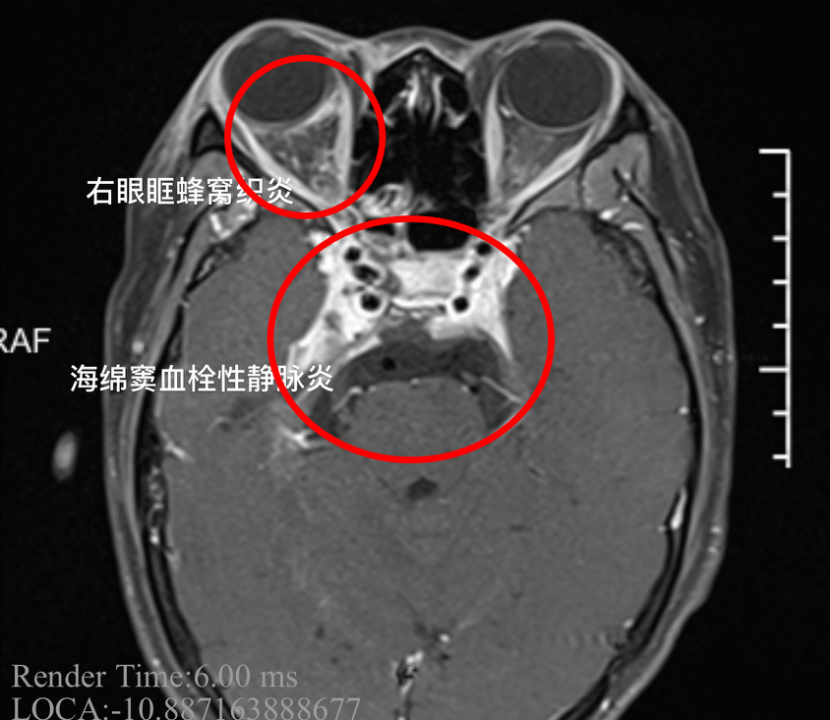

经过诊断,小杨患上了“海绵窦血栓性静脉炎”,这是一种严重的颅内感染。这种病如果没有得到及时治疗,可导致患者死亡。

医院接诊的神经内一科副主任医师韩锟说:“患者刚来的时候,病情是比较严重的,体温持续在39℃以上。女孩的右眼外凸,眼球已经固定无法转动,瞳孔扩大,对光反射消失,多组颅神经受累。这都是海绵窦严重感染的征象。同时我们发现患者的脑膜刺激征阳性,海绵窦的炎症已经扩散,出现了脑膜炎,继续进展随时有生命危险。”